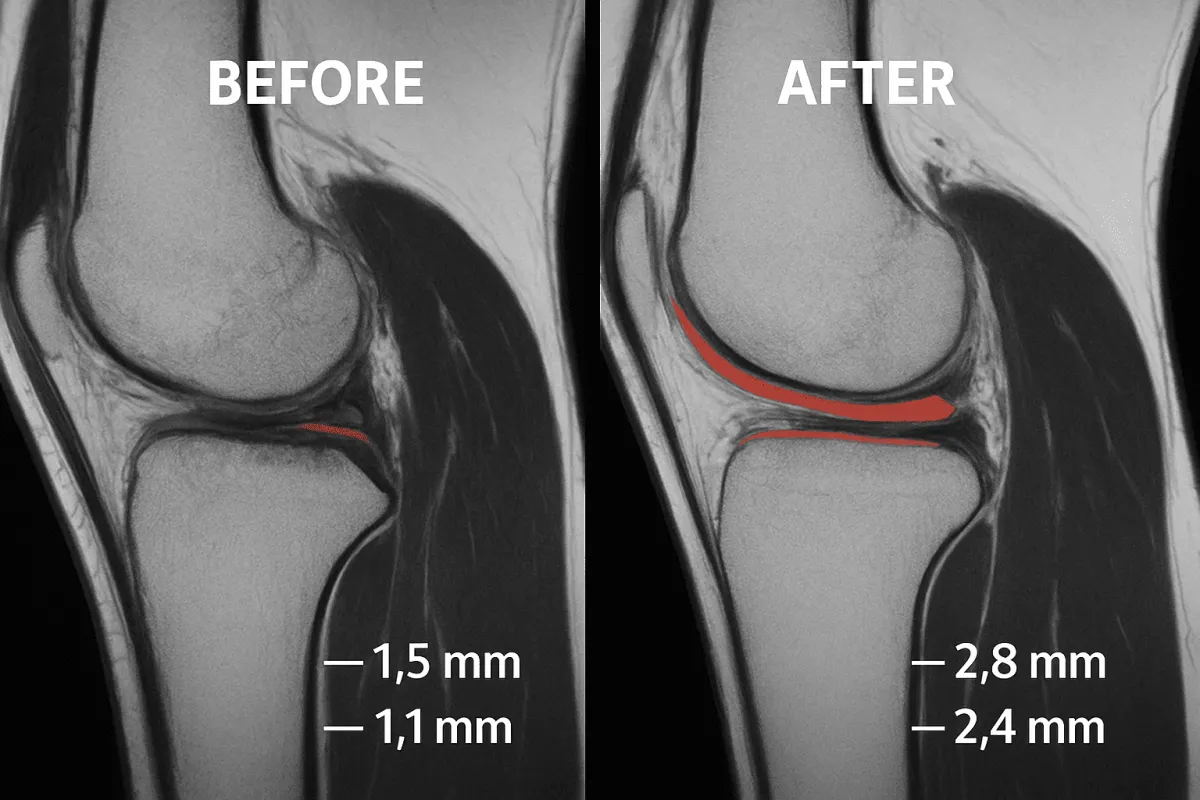

Nonostante i pregiudizi secondo cui la cartilagine non possa rigenerare, le cellule staminali mesenchimali dimostrano di ridurre dolore e favorire la ricostruzione articolare nelle fasi iniziali dell’artrosi.